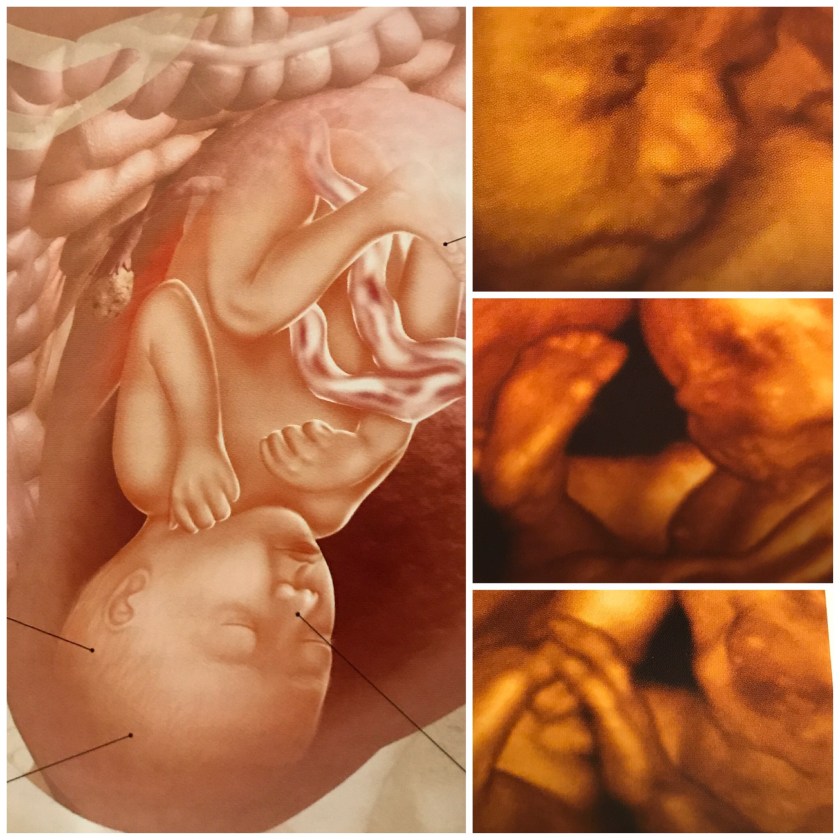

Our baby today is 29 weeks, about 15 inches, the size of a large butternut squash and weighing 2 1/2 pounds. For size comparison, I put a squash next to my filtered water bottle that holds 26 ounces of water.

His or her lungs, bones and muscles are growing bigger this week, making my food choices more important.

Additionally our baby’s head is getting bigger to accommodate his or her growing brain.